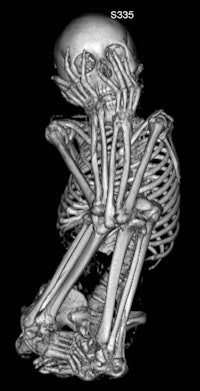

| A 13-year-old female mummy. Images courtesy of Dr. Klaus Friedrich. |

Sex and age of the mummies were determined by analyzing body structures such as the pelvis and skull, the authors wrote. Eight mummies were identified as female, three as male, and sex could not be determined for one. The ages of the mummies were newborn, 0.7 years, 2.5 years, 13 years, 13 years, and 16 years, with six mummies identified as being between 20 and 40 years old.

The height of the mummies, estimated by measuring femur and tibia length, ranged from 41 ± 3 cm (newborn) to 145 ± 14 cm (adult).